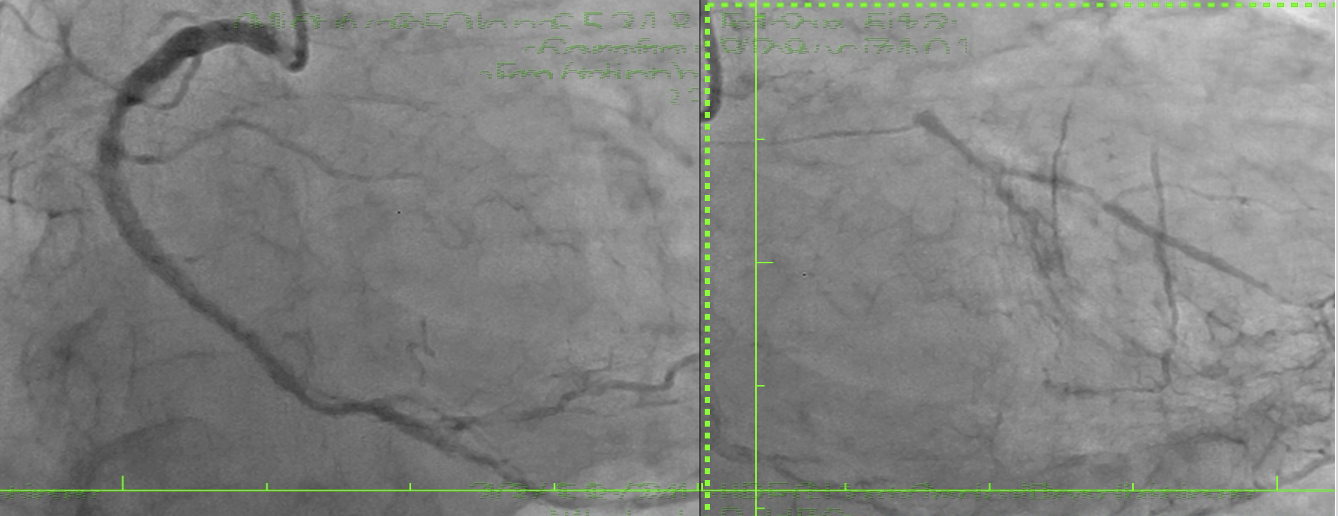

Same-day coronary angiography revealed diffuse disease in the right coronary artery providing collaterals to the LCx and LAD. A subocclusive distal left main stenosis extended into the LAD. Despite a high Syntax score (33) favoring bypass, the patient opted for percutaneous treatment. A key challenge was locating the LCx ostium, which was angiographically silent, with only a thin channel guiding the wire toward the LAD, complicating LCx access.

The procedure commenced with IABP insertion and the use of a 7F XB guiding catheter for an antegrade approach. A wire was advanced across the LM-LAD stenosis, and predilatation with a 2.5 mm semicompliant (SC) balloon revealed the faint ostium of the occluded LCx. A 45¡Æ angulated microcatheter facilitated the crossing of the LCx occlusion with a stiff wire, which was then exchanged for a standard workhorse wire.Following LCx predilatation, kissing balloon pre-dilation of the LM-LAD-LCx bifurcation was performed. A 3.0x18 mm Sirolimus stent was deployed in the proximal LAD. Subsequently, a 2.75x18 mm Sirolimus stent was placed in the LCx with minimal protrusion into the LM and crushed with a 3.5 mm non-compliant (NC) balloon. The crushed stent struts were recrossed, predilated with sequential SC balloons, and a distal optimization (DOT) was performed. A second kissing balloon inflation followed.A third Sirolimus stent (4.0x25 mm) was then overlapped with the previous stent in the LAD-LM segment. After a proximal optimization technique (POT) in the LM, the LCx was rewired. Final optimization included further DOT in both the LAD and LCx, a final triple kissing balloon inflation, and a concluding POT. An excellent final result was confirmed by IVUS (LAD area 9.2 mm©÷; LCx area 8.1 mm©÷; minimal lumen area 16 mm©÷) and angiography, after which the IABP was removed.